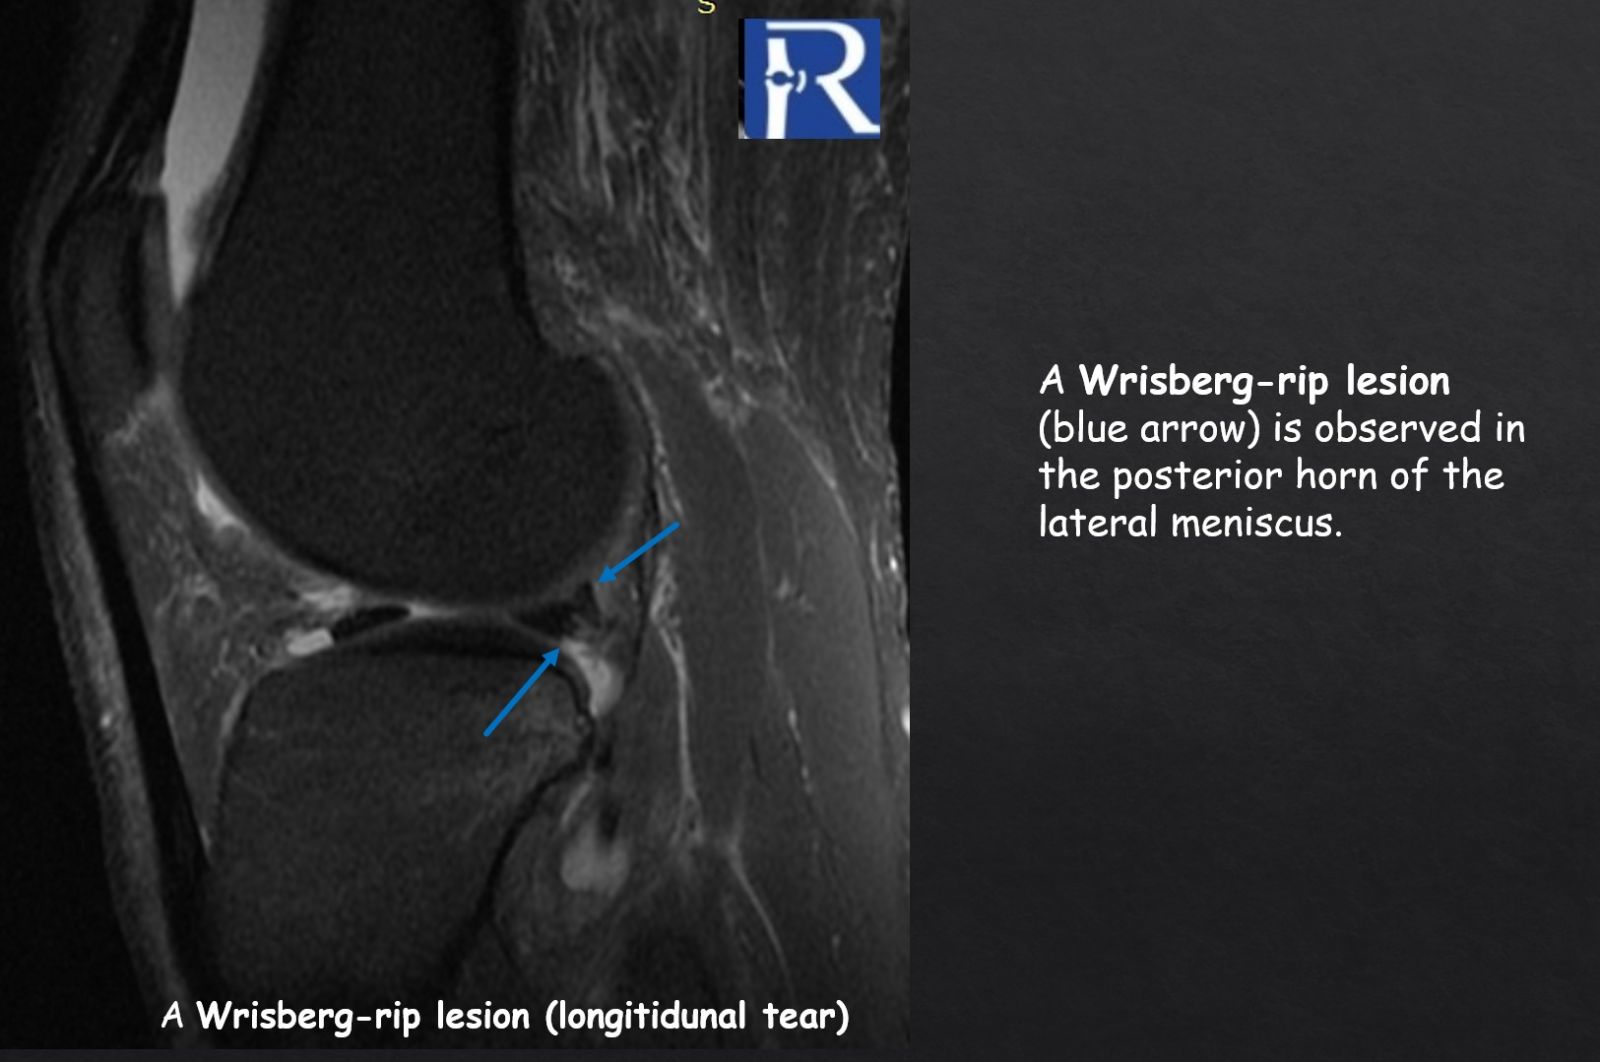

- Posterior horn lateral meniscus Wrisberg-rip tear